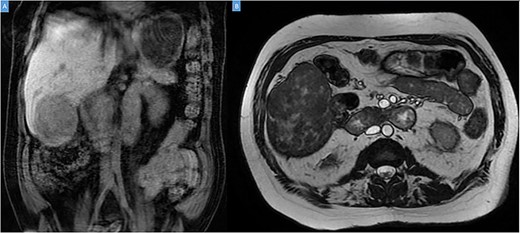

A 49-year-old male presented with a large right hepatic lobe mass on abdominal computed tomography (CT) scan ordered for non-specific abdominal pain. He had a past medical history of type 2 diabetes mellitus, glaucoma and deafness due to mumps. The physical examination was normal, with a body mass index of 22 kg/m2 and no previous abdominal surgeries. CT scan (Fig. 1A and B) and magnetic resonance imaging (MRI; Fig. 2A and B) revealed a 10.7 × 7.6 × 8.9-cm mass involving the liver’s segments V–VI with heterogeneous enhancement and areas of calcification.

Coronal (A) and axial (B) sections of MRI showing the peripheral liver tumor.